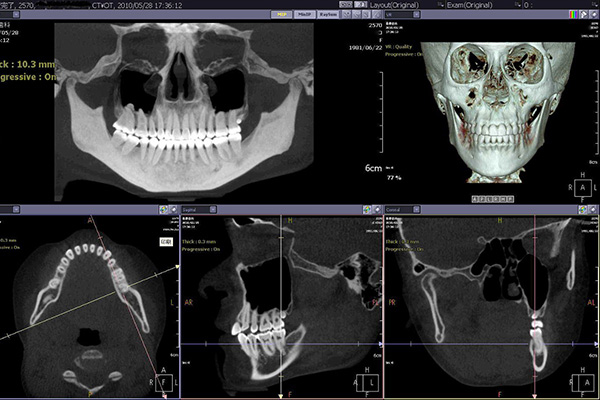

CT検査により根尖病変や歯の破折の発見、インプラント治療での骨の状態、神経、血管の正確な位置関係、親知らずの難抜歯における事前検査など、レントゲン検査だけでは把握不可能な情報を3次元画像で得る事ができます。特に口腔外科では、事前に3次元情報を把握する事で様々なリスクを回避する事が可能となります。